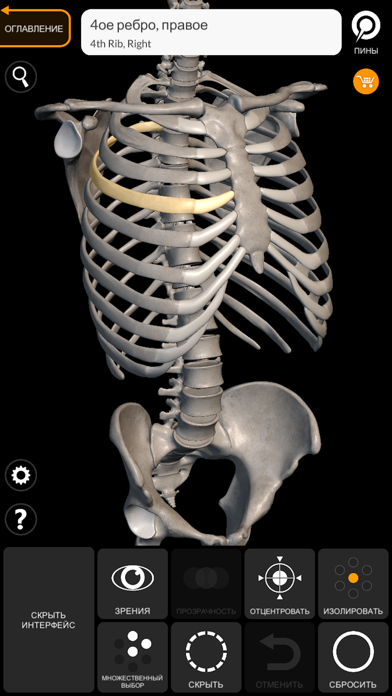

Скриншоты